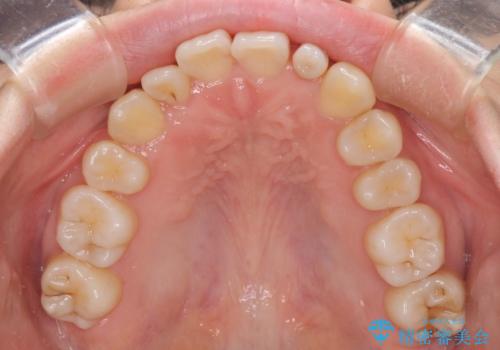

インビザライン単体での治療は困難と判断し、補助装置により八重歯移動後にインビザラインを用いることとしました。

非常にしっかりとマウスピースを装着してくださいましたが、前歯の排列がなかなか仕上がらずに期間がかかってしまいました。